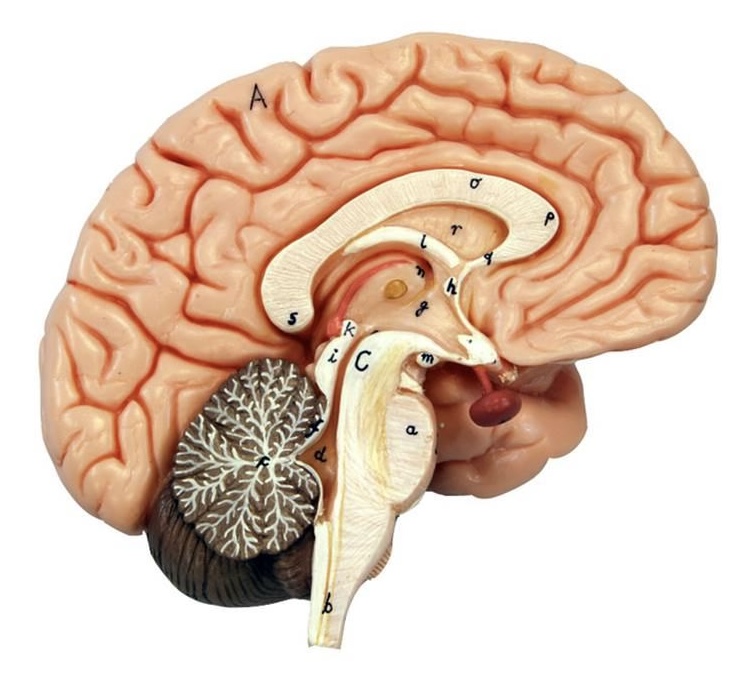

What is D?

lateral ventricle

Imagine thin membrane separating the 2 lateral ventricles

septum pellucidum

What is C?

3rd ventricle

What is B?

cerebral aqueduct

What is A?

4th ventricle

What is below A at the very end?

central canal (spinal cord)

What is C?

midbrain

tectum (corpora quadrigemina): superior colliculus

tectum (corpora quadrigemina): inferior colliculus

What is a?

pons

medulla oblongata

intermediate mass of thalamus

hypothalamus

What is the pink bulb?

pineal gland

corpus callosum

fornix

What is A?

cerebral cortex

cerebral tracts

cerebral hemispheres

longitudinal fissure

What are these ridges?

gyri

What are these shallow grooves?

sulci

Divides parietal from frontal lobe

central sulcus

precentral gyrus

postcentral gyrus